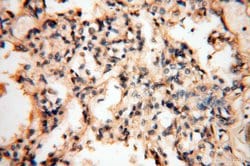

SYK Rabbit anti-Human, Mouse, Rat, Polyclonal, Proteintech

This gene encodes a member of the family of non-receptor type Tyr protein kinases. This protein is widely expressed in hematopoietic cells and is involved in coupling activated immunoreceptors to downstream signaling events that mediate diverse cellular responses, including proliferation, differentiation, and phagocytosis. It is thought to be a modulator of epithelial cell growth and a potential tumor suppressor in human breast carcinomas. Alternatively spliced transcript variants encoding different isoforms have been found for this gene.Specifications

| Immunohistochemistry (Paraffin) | |